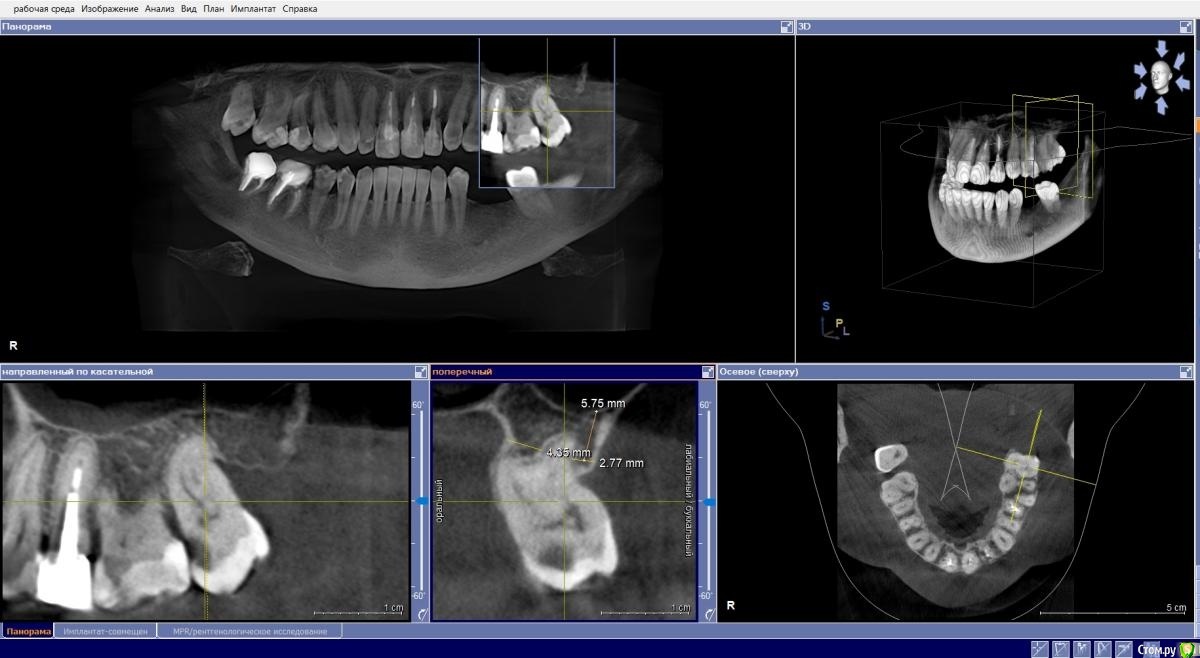

Евгений Ходыкин Опубликовано 10 ноября, 2020 Поделиться Опубликовано 10 ноября, 2020 Нет тут места и на щит, и на имплантат Ссылка на комментарий

Fin Опубликовано 10 ноября, 2020 Автор Поделиться Опубликовано 10 ноября, 2020 (изменено) Нет тут места и на щит, и на имплантатНе понял Вас. Между корнями около 8 мм , 3.5 должен пройти. Больше беспокоит что после полного удаления корня образуется перфорация кортикальной стенки. Изменено 10 ноября, 2020 пользователем Fin Ссылка на комментарий

Евгений Ходыкин Опубликовано 11 ноября, 2020 Поделиться Опубликовано 11 ноября, 2020 Не понял Вас. Между корнями около 8 мм , 3.5 должен пройти. Больше беспокоит что после полного удаления корня образуется перфорация кортикальной стенки.В вестибуло-оральном направлении имею ввиду Ссылка на комментарий

Fin Опубликовано 11 ноября, 2020 Автор Поделиться Опубликовано 11 ноября, 2020 (изменено) В вестибуло-оральном направлении имею ввидуНе могли бы поподробнее разъяснить? Не понимаю в чём может быть подвох. Изменено 11 ноября, 2020 пользователем Fin Ссылка на комментарий